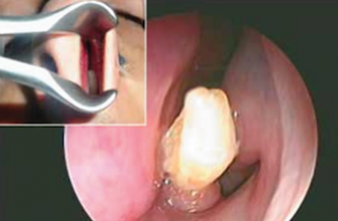

Un jeune saoudien qui se plaignait de saignements de nez réguliers depuis trois ans a fait une découverte surprenante. A 22 ans, il avait toutes ses dents et même plus, puisqu’une sorte de prémolaire d’un centimètre de long lui poussait dans les narines. Un cas insolite publié il y a quelques jours dans la revue scientifique American Journal of Case Reports.

Opéré sous anesthésie générale dans un hôpital de Dhahran (Est du pays) après cette découverte, les médecins ont fait le choix de lui retirer cette dent cachée au fond de sa narine gauche. Un choix judicieux, puisque depuis l'intervention l’homme n’a plus de saignements de nez.

Pour les médecins qui l'ont opéré, la découverte de cette dent a été particulièrement surprenante car l'homme en question avait des dents bien alignées et de taille normale.